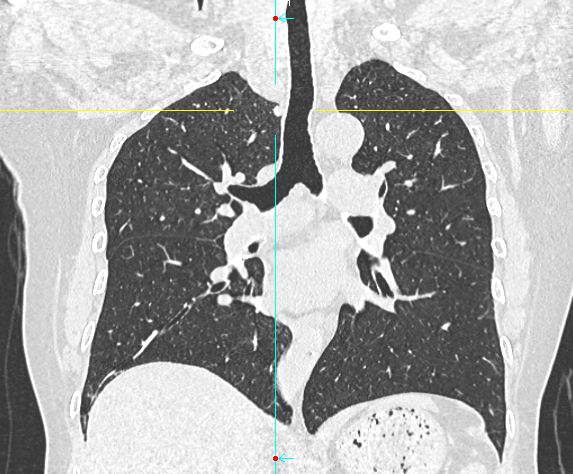

数月前,66岁的龚女士在肺癌术后随访复查中,胸部CT报告显示其右上肺新发实性结节一枚,并由刚开始发现时的5mm逐步增大至10mm。更棘手的是,这个结节位于右肺上叶尖段的纵隔胸膜下,位置极其“刁钻”。面对这份报告,患者龚女士陷入了深深的焦虑。因为其7年前因右中肺肿瘤行右中肺癌根治术,对于新发的实性结节为何种性质,是新发肺恶性肿瘤或是良性病变,亦或是原肺癌复发转移,目前均不能明确。辗转多家医院,得到的建议多为“定期观察,等待变化”或考虑创伤较大的传统穿刺活检,但结节位置非常深,单纯CT引导下定位穿刺很难精准到达,且需穿行的肺组织较多,创伤较大。

胸外科马海涛主任团队对龚女士的病情进行了深入细致的评估:结节虽小,但形态学特征具有风险,且结节逐步增大,结合既往肺癌病史,考虑肿瘤复发可能,“定期观察”方案会让患者持续承受心理煎熬。然而,传统的CT引导下经皮肺穿刺定位,对于如此深部、微小的结节,极易导致气胸、出血等并发症,风险极高。

马主任解释系统原理:“这套系统就像为我们医生的操作装上了‘肺部GPS’。它通过术前将患者的CT影像数据导入系统,构建出独一无二的肺部三维‘地图’。术中,在磁场的引导下,我们操控一根细如发丝的导航探头,经由患者的口腔、气管这一自然通道,毫无创伤地直达常规支气管镜无法到达的肺外周深处,精准地停靠在目标结节旁边。磁导航支气管镜的优势是决定性的。它实现了‘经自然腔道、无创抵达’,彻底避免了经皮穿刺可能引起的高达20%-30%的气胸风险,为定位深部结节提供了安全、精准的解决方案。”